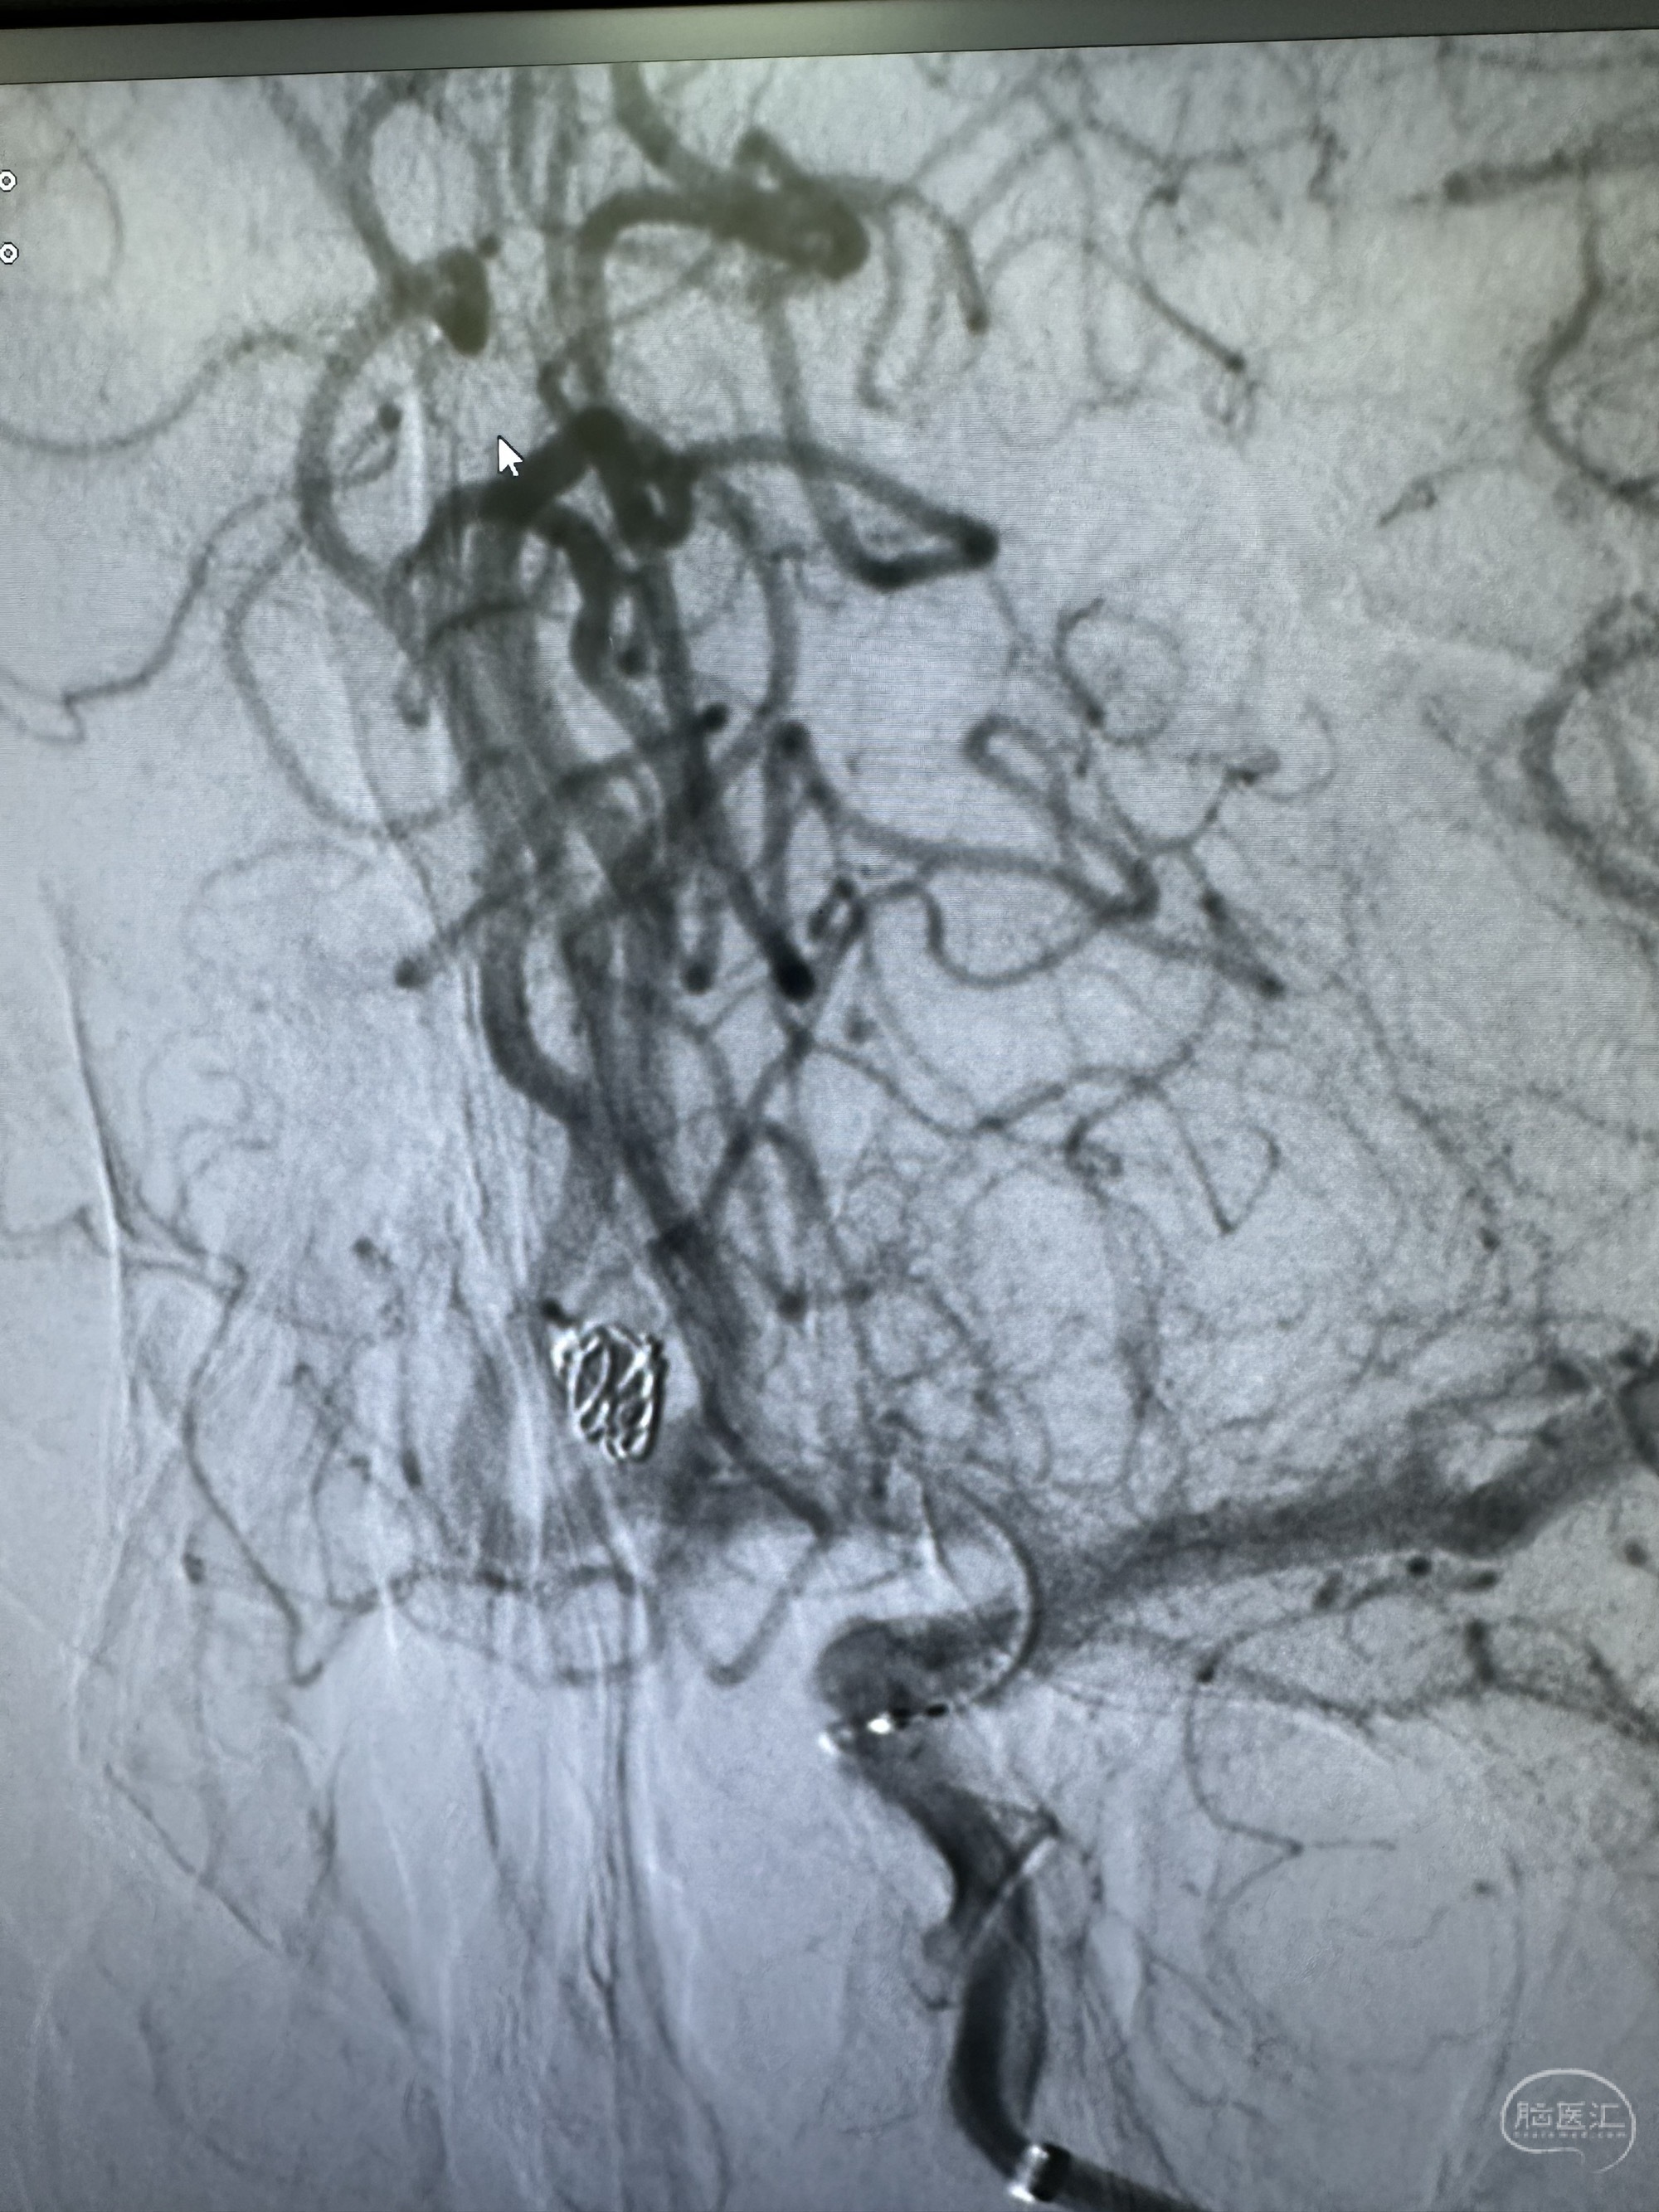

第一枚圈选择4*8的target 3D

圈的形态

后续填塞三枚ES 3*8,1.5*3,1*3.

最后圈的形态